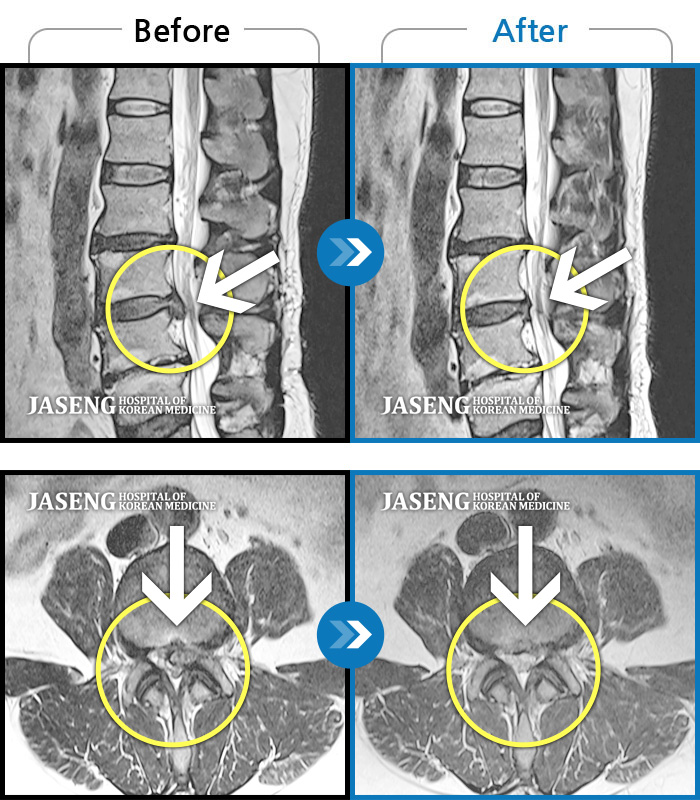

허리디스크

광주 · 김동은 원장

허리부터 골반 및 우측 허벅지에서 발가락까지 묵직한 통증과 저림 발생하여 내원하셨습니다.

촬영시기

2022.07.22 ~ 2025.08.18

2025.08.22